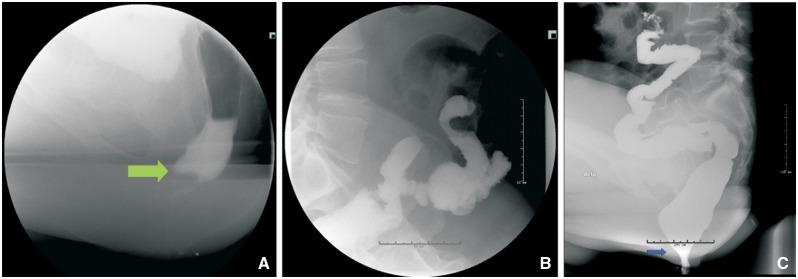

Restorative proctocolectomy with ileal pouch-anal anastomosis has become the surgical treatment of choice for patients with refractory ulcerative colitis, colitis-associated dysplasia or familial adenomatous polyposis. There are various pouch disorders and associated complications. Floppy pouch complex is defined as the presence of pouch prolapse, afferent limb syndrome, enterocele, redundant loop and folding pouch on pouchoscopy, gastrografin pouchogram or defecography. Common clinical presentation includes dyschezia, bloating, abdominal pain, straining or the sense of incomplete evacuation. Each disorder has its own unique endoscopic, radiographic and manometry findings. A range of therapeutic options are available for the management of the various causes of a pouch.

回肠袋肛管吻合术式的全直肠系膜切除术已成为难治性溃疡性结肠炎、结肠炎相关发育异常或家族性腺瘤性息肉病患者的首选手术治疗方式。存在多种袋状病变及相关并发症。松弛袋综合征的定义为在袋状内镜检查、泛影葡胺袋造影或排粪造影时出现袋脱垂、输入袢综合征、肠膨出、冗长肠袢及折叠袋。常见临床表现包括排便困难、腹胀、腹痛、用力排便或排便不尽感。每种病变都有其独特的内镜、影像学及测压表现。对于袋状病变的各种病因,有一系列治疗选择可供采用。